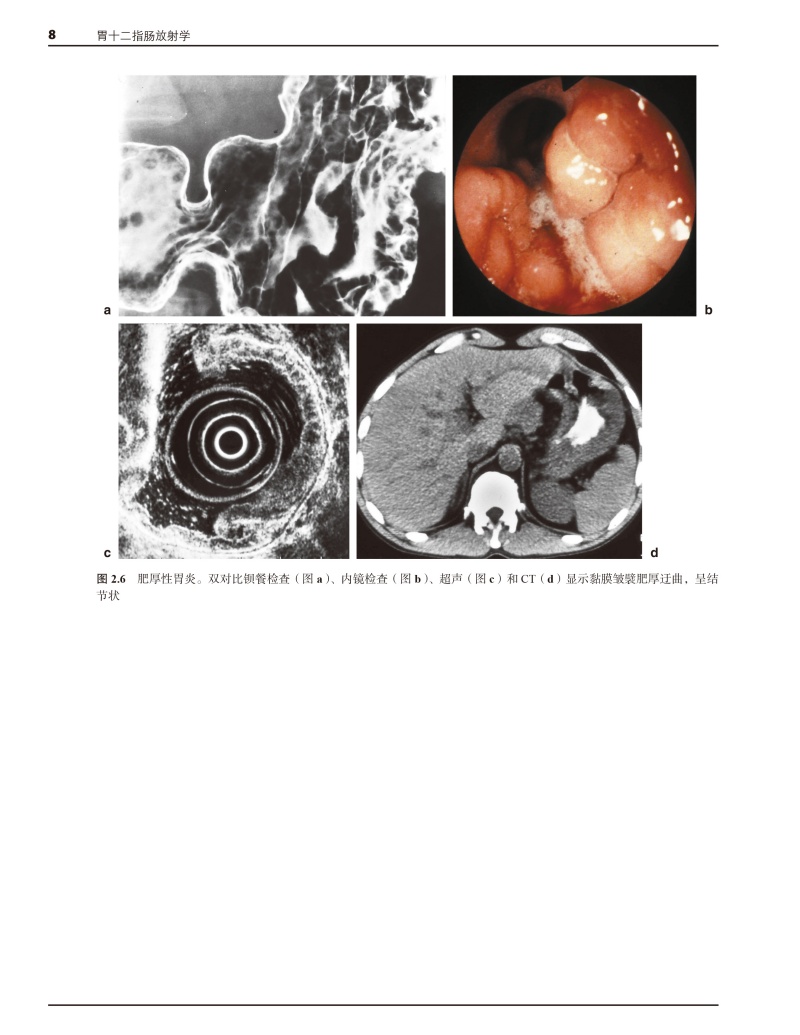

本书由英国剑桥大学医学院A.H.Freeman先生和E.Sala女士主编,是一部基于多学科诊治框架的胃十二指肠放射学专著。该书对胃、十二指肠疾的解剖、生理、病理、内镜、超声内镜、钡餐造影、CT、磁共振成像、同位素检查和介入放射学等方面进行了系统、深入的阐述,并结合具体案例对重要的临床问题进行剖析和总结。本书由中山大学附属第五医院张亚琴教授、暨南大学附属华侨医院史长征教授、江门中心医院崔恩铭教授和南方医科大学南方医院吴元魁教授共同主持和消化内科、胃肠外科、血管介入、核医学科、影像科医师参与,历经3年对原著进行了翻译。是一部这是一部具有很高学术价值而且实用性很强的专著。

结合具体案例对胃、十二指肠疾的解剖、生理、病理、内镜、超声内镜、钡餐造影、CT、磁共振成像、同位素检查和介入放射学等方面进行系统、深入的阐述